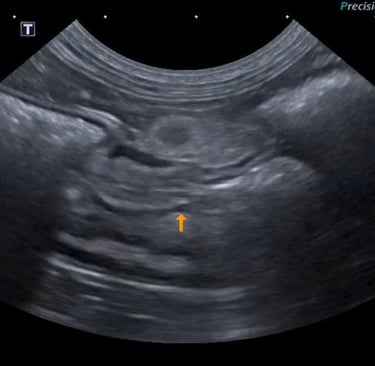

4 - Est ce que l’image obtenue vous semble correcte ?

A - Oui

B - Non

C - Je ne sais pas

5- Si non, expliquez quel réglage serait intéressant de modifier pour obtenir une image échographique correcte

A - J'ai coché oui à la réponse précédente

B - Diminuer la profondeur

C - Augmenter la profondeur

D - Augmenter le gain étagé en profondeur

E - Diminuer le gain étagé en profondeur

6- De quel organe s’agit-il ? Précisez G ou D et le plan de coupe réalisé

A - Le Rein Gauche en coupe transversale

B - Le Rein Droit en coupe transversale

C - Le Rein Gauche en coupe longitudinale

D - Le Rein Droit en coupe longitudinale

E - La Surrénale droite en coupe transversale

7 - En sachant que l'autre rein présente le même aspect échographique, et qu'ils mesurent tous les deux 3,5 cm de long, vous pouvez conclure :

A - Absence d'anomalie échographique visible

B - Nephromégalie bilatérale

C - Dilatation de la cavité pyélique

D - Signes échographiques en faveur d'une néphrite tubule-interstitielle

E - Signes échographiques en faveur d'une glomerulonephrite

Question 4 : Réponse B

Question 5 : Réponse B

Question 6 : Réponse C

Question 7 : Réponse A